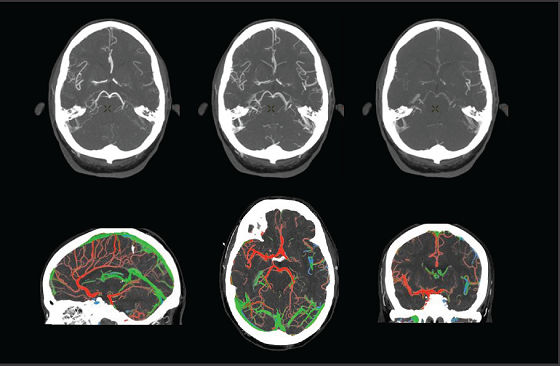

A patient with suspected TIA or stroke receives a general and neurological examination followed by diagnostic brain imaging, performed immediately on arrival so that treatment can be started promptly. 3 Optimal scanning coupled with workflow applications and protocols designed for stroke help deliver accurate and quick diagnosis to impact patient outcomes.

<p>Revolution brand of CT systems</p>

Read More

<p>FastStroke CT Application</p>

<p>Fast Brain protocol with HyperWorks</p>